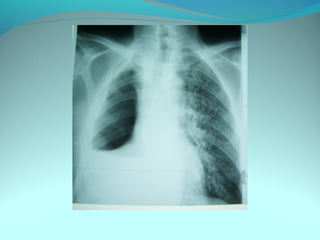

Opacité triangulaire a base cardiaque a sommet

axillaire dense et homogène

Par ailleurs on note

Une opacité plus dense que celle arrondie de 3cm de

diam hilaire gauche ;une surélévation de la coupole

diaphragmatique gauche é poche a aire gastrique

DIAGNOSTIC :

ADP hilaire gauche avec trouble de ventilation

Surelevation de la coupole G et de la poche gastrique

avec de clarté le médiastin

DIAGNOSTIC:

Hernie diaphragmatique paralysie du diaphragme